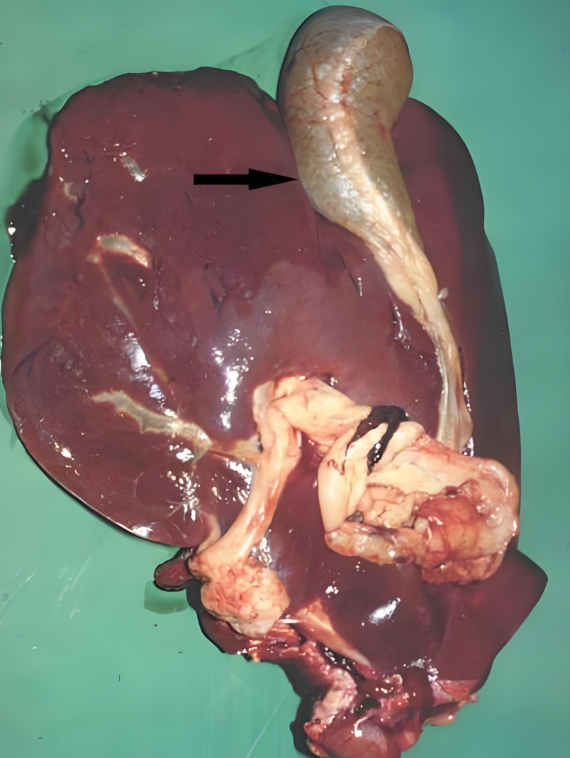

对牧区和低洼地带的养殖户来说,牛羊肝片吸虫病是常年悬着的 “隐患”—— 它不仅是牛羊的 “健康杀手”,导致消瘦、产奶下降甚至死亡,还是人畜共患病,人若生食受污染的水生植物、鱼虾也可能感染。掌握这种病的 “识别 - 防控 - 治疗” 全流程,是养殖户减少经济损失、保障养殖安全的关键。本文结合临床实践,拆解牛羊肝片吸虫病的科学应对方案,让养殖户能 “看得懂、用得上”。

2. 症状:急慢有别,这些 “信号” 别忽视

肝片吸虫病的症状分急性、慢性和典型表现,不同阶段症状差异明显,需针对性判断: